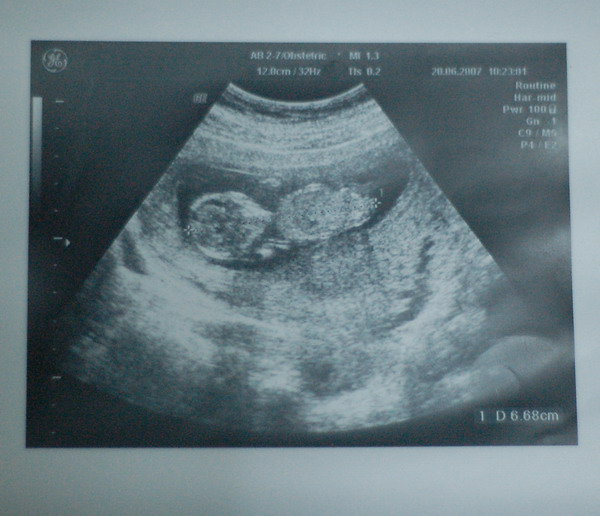

| Maggiealan 水水 我們有同樣的困擾勒^^" 上次在這邊問過大家意見後~ 我又到其他討論區去爬文... 發現~在大雅路上的正馨婦產科還不錯喔! 看完診後醫生拿了兩張超音波照讓我選.. 感覺比林新清楚多了... 聽說正馨還會免費幫孕婦照4D.. 不過~我這回去沒有照到啦! 正馨的醫生看診也滿仔細的.. 讓我現在很猶豫... 到底是該繼續在林新產檢偶爾到正馨拍超音波照就好~ 還是要直接換到正馨產檢.. 可是~總覺得還是在醫院生產比較安心= =" PS.底下的照片就是在正馨拿到的 |

![]() |